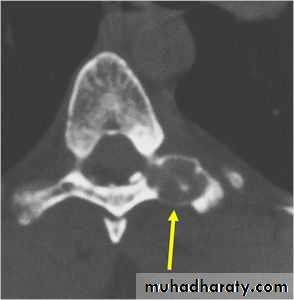

Osteoblastoma (giant osteoid osteoma):

It’s benign and similar to osteoid osteoma but its larger and more cellular.It occurs in young adults, males more than females.

Its commoner in the spine and flat bones& usually presents as pain or muscle spasm.

X-ray shows well-defined lytic lesion surrounded by thin zone of sclerosis, it may contain flecks of calcification.

Treatment consists of excision and bone grafting. With lesions in the vertebral pedicle or the floor of the acetabulum, this is not always easy and removal may be incomplete.

local recurrence is common, and malignant transformation has been reported